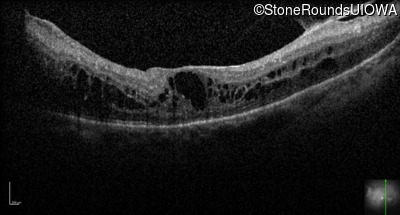

Optical Coherence Tomography - Right - 20/50 -2

Exemplar / OCT Stack

OCT Stack